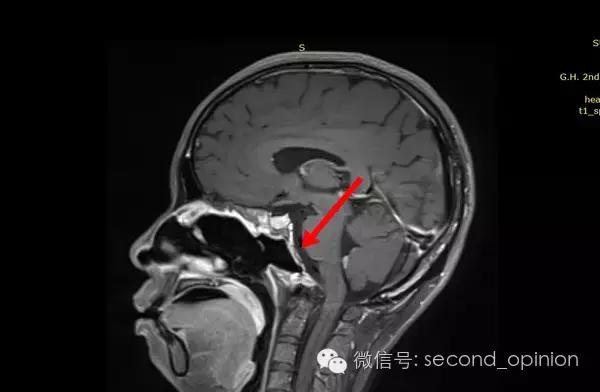

患者自2013年6月起无诱因出现吞咽困难,伴吐字不清症状,自觉舌肌无力一个星期,偶有头痛发作,不伴呛咳,呕吐,无抽搐发作。当时耳鼻喉科做相关检查,咽部无异常表现。行头部CT检查发现颅内占位,范围约43*30mm。保守治疗,后病情稳定,未发现症状明显加重。

至2014年1月,出现左耳耳鸣,表现为低调杂音,未发现听力明显下降,偶有脸部麻木,无面瘫。行MRI检查,颅内占位范围约60*45*47mm。2014年2月2日第一次手术,行内镜导航下经蝶窦颅底肿瘤切除术,切除体积约50*45*50mm,手术顺利,术后头痛症状消失。左耳低调耳鸣术后消失两周后再次出现,右耳术后出现偶发轻度耳鸣。2014年5月4日第二次手术,行内镜口鼻蝶入路脊索瘤切除术,切除肿瘤体积45*40*50mm,过程顺利,术后耳鸣消失,病情稳定后出院。

2014年6月15日 进行射波刀放疗,32.5Gy/5fx,剂量曲线69%包绕,治疗期间对症脱水,减轻放疗反应,完成全部治疗后出院。

2014年12月 进行质子放射治疗。

病理结果:脊索瘤

免疫组化:CK+、vimentin+、S-100-、CK8/18+、Ki-67约10%、EMA+

质子治疗:

日本国立癌症中心 2014年12月3日-12月31日

总剂量40GyE

2014年9月1日MRI(手术治疗前)

质子治疗前

2015年1月25日 对比质子治疗之前增强核磁共振影像无明显变化,脊索瘤放疗后变化缓慢,建议3月后继续复查。

2015年04月01日 对比增强核磁共振影像,同第一次复查。

2015年06月03日 对比增强核磁共振影像,对比第三次复查,肿瘤略有缩小。

质子治疗后第四次复查

目前患者生活质量良好,无复发转移。